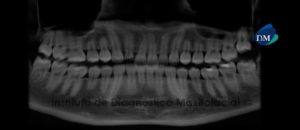

Paciente masculino, 12 años de edad es referido al Instituto de Diagnóstico Maxilofacial (IDM) para evaluación general.A la evaluación de la radiografía panorámica se aprecia